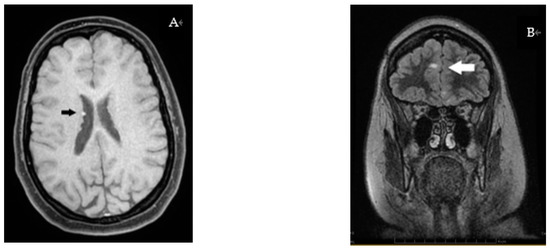

3.3. Radiology Investigations